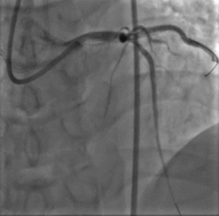

取0.014" Runthrough NS导丝通过病变送入高位钝缘支远端(图4),送入Atlantis SR血管内超声导管至左主干远段,未见明确前降支开口影像,0.014" Sion导丝未能通过前降支近段支架内闭塞病变处,换用0.014" ConquestPro导丝成功通过前降支近段支架内闭塞病变送至前降支中段(图5、6),换入0.014" Sion导丝至前降支远端,Sprinter Legend 2.5×15 mm球囊锚定导丝后,再以该球囊成功通过闭塞病变,反复以10~12 atm×5 s扩张(图7)。复查造影显示前降支恢复TIMI 3级血流,前降支近段处残余狭窄50%,中段局限性狭窄70%(图8)。Sprinter Legend 2.5×15 mm球囊以6 atm×8 s扩张前降支中段病变后,送入IVUS导管至前降支中段连续自动回撤示前降支中段心肌桥征象,近段弥漫性纤维斑块形成。植入Buma 3.5×25 mm雷帕霉素药物支架以10 atm×8 s扩张释放(图9),稍前送该支架球囊至两支架交界处以10 atm×8 s再次扩张塑形。行IVUS检查左主干内支架贴壁不良。取Quantum 4.5×12 mm高压球囊至左主干支架内以14~20 atm×8 s扩张塑形(图11),复查造影示支架扩张满意,残余狭窄<30%,血流TIMI 3级,回旋支血流未受影响(图12)。复查血管内超声示支架扩张满意,贴壁良好,支架两端无夹层征象。

图4